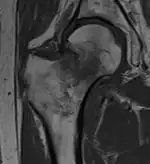

Typically, radiographs are taken of the hip from the front (AP view), and side (lateral view). Frog leg views are to be avoided, as they may cause severe pain and further displace the fracture.[5] In situations where a hip fracture is suspected but not obvious on x-ray, an MRI is the next test of choice. If an MRI is not available or the patient can not be placed into the scanner a CT may be used as a substitute. MRI sensitivity for radiographically occult fracture is greater than CT. Bone scan is another useful alternative however substantial drawbacks include decreased sensitivity, early false negative results and decreased conspicuity of findings due to age-related metabolic changes in the elderly.[16]

A case demonstrating a possible order of imaging in initially subtle findings: